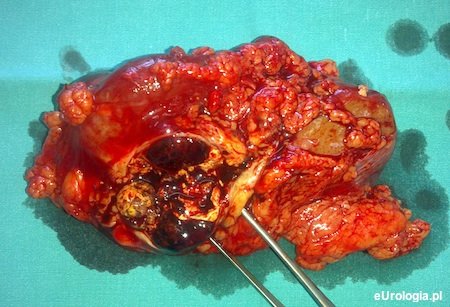

Fot. Torbiel nerki 4 kategorii według Bosniaka. W tomografii komputerowej liczne grube przegrody oraz masy wzmacniające się po podaniu kontrastu. W wyniku histopatologicznym zmiana złośliwa.

Kategoria IV torbieli w klasyfikacji Bosniaka

Masa torbielowata widoczna w badaniach obrazowych posiadająca cechy kategorii III według klasyfikacji Bosniaka z obecnością miękkich tkanek wzmacniających się po podaniu kontrastu. Zalecane jest leczenie operacyjne - zdecydowana większość zmian to zmiany złośliwe.